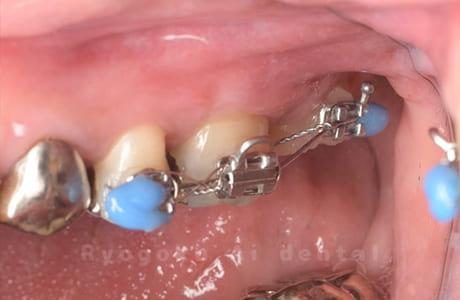

他院で抜歯と宣告され、セカンドオピニオンでご来院された患者様です。右上の8番を右上の7番にスライド移植し、部分矯正で理想的な位置にもっていきました。患者様も満足されています。